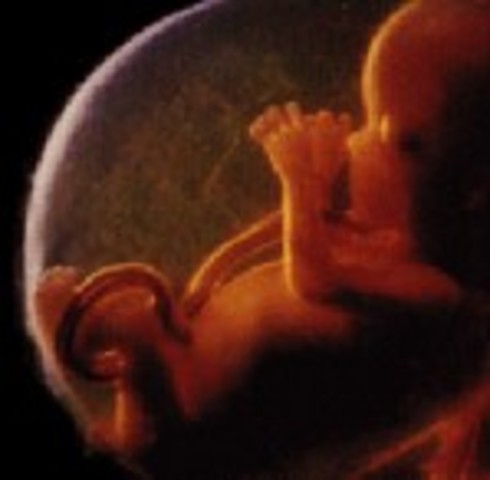

• Week 27

Week 27

This is the start of the third trimester and the look of the baby will be the same at birth. The brain is rapidly growing, and the retina of the eyes are developing.